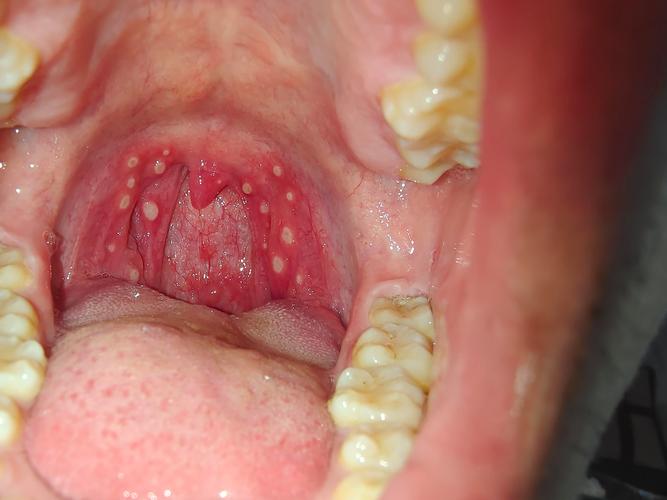

嗓子口腔溃疡了怎么办?

非常理解您的痛苦,嗓子疼加上口腔溃疡,真是“双剑合璧”,吃饭喝水都像受刑,别担心,这种情况很常见,通常是由病毒感染、免疫力下降、压力或上火等多种因素引起的。

虽然大多数口腔溃疡会在一到两周内自愈,但如果出现以下“警报信号”,请及时就医:

- 溃疡面积巨大:直径超过1厘米,或形态不规则。

- 数量多:嘴里出现十几个甚至几十个小溃疡。

- 持续时间过长:超过3周仍未愈合,甚至越来越严重。

- 疼痛剧烈到无法进食:导致无法进食进水,有脱水的风险。

- 伴随全身症状:如发烧、皮疹、关节痛、腹泻等。

- 反复发作:溃疡刚愈合不久,在同一个或不同位置又长出来了,频率很高。

- 溃疡位置特殊:长在嘴唇边缘,可能是疱疹病毒(俗称“上火起泡”)。